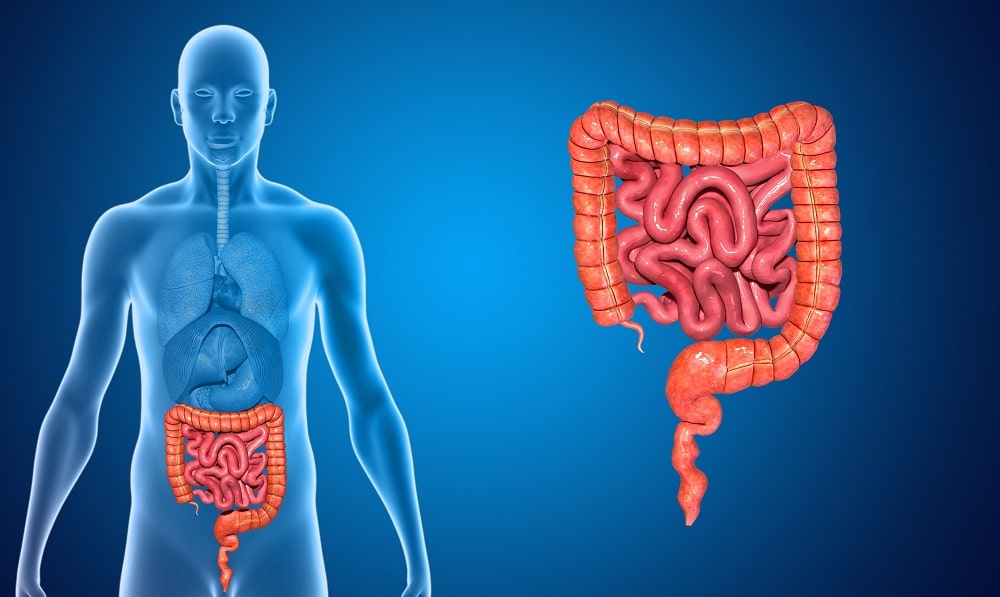

A joint is where two or more bones “join”, or meet, connected by ligaments and muscles for stability.

Cartilage, the smooth, connective tissue covering the ends of the joint bones, allows them to glide over each other when they move and helps distribute compression forces.1

“Arthritis” means joint inflammation, but the term often refers to joint disorders broadly. There are many types of arthritis; the most common, especially among older people, is osteoarthritis. In this condition, the cartilage wears away, causing the bones to rub together and leading to pain, swelling and loss of motion.